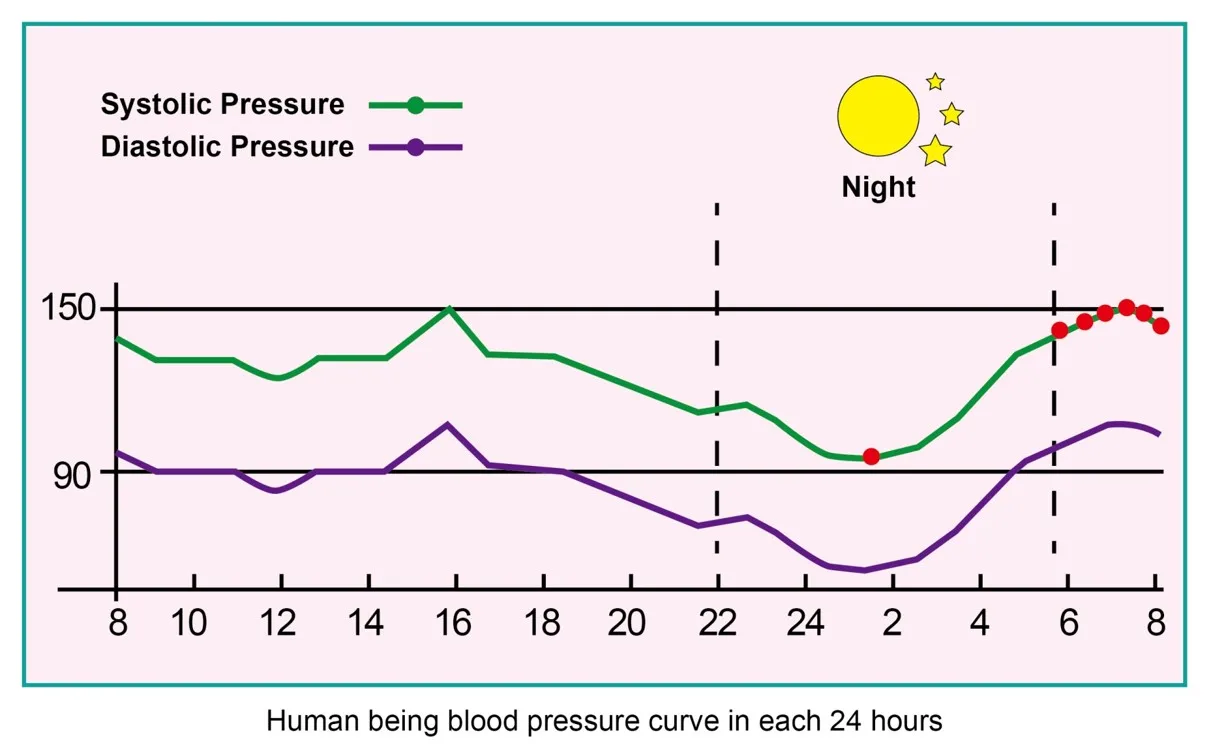

Application: Wrist

Bluetooth: Yes

Brand Name: komwell

Certification: CE

Choice: yes

Data Storage: Yes

Function: Blood pressure,ecg,Oximetry

Hign-concerned Chemical: None

Is Batteries Included: Yes

Item Type: blood pressure

Model Number: BPW1

Origin: China Mainland

System support: Bluetooth4.0 for iOS and Android

komwell Model: W1

languages: 17 languages can be freely converted

semi_Choice: yes

voice: Y